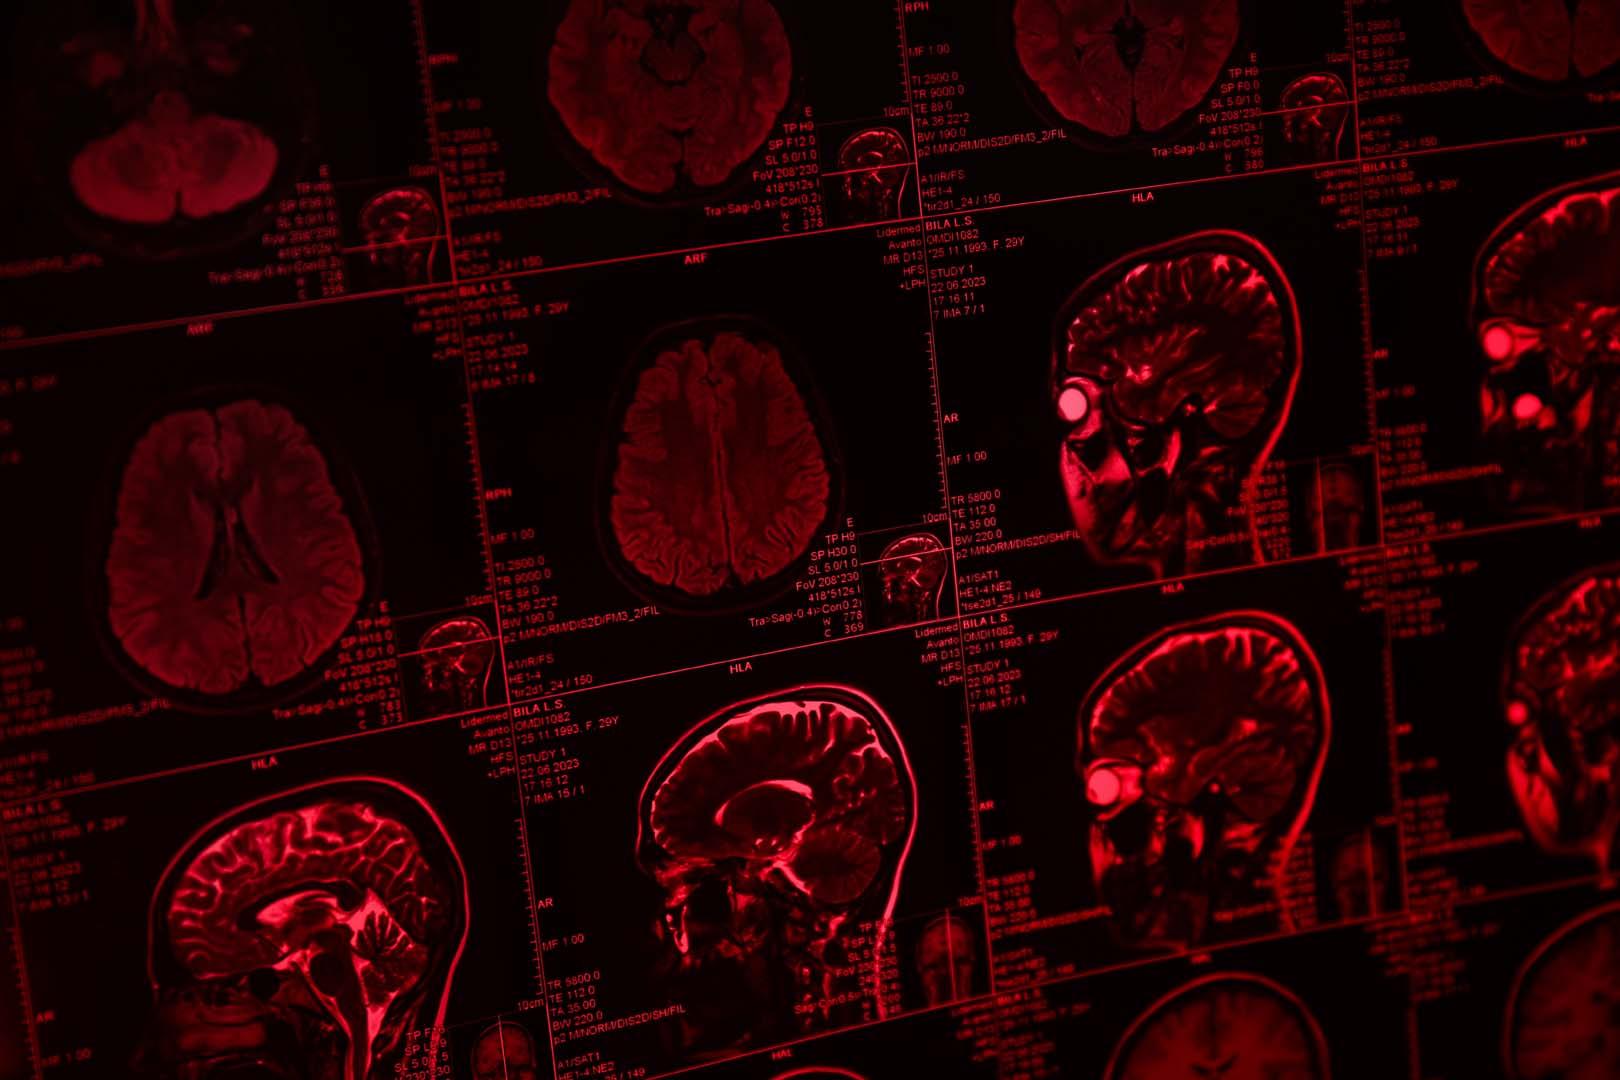

Manchester Üniversitesi'ndeki bilim insanları, Danimarka'daki ekiplerle iş birliği yaparak beyin tümörlerinin tespitinde çığır açacak bir kan testi geliştirdi. Bu yeni test, özellikle agresif glioblastoma vakalarında, yüzde 90'ın üzerinde doğruluk oranı sunuyor. Şu an için tanı ve takip süreci zorlu cerrahi biyopsiler ve kapsamlı MRI taramaları gerektirirken, geliştirilen kan testi sayesinde aile hekimleri hastalığı çok daha erken ve kolay bir şekilde saptayabilecek. Araştırmanın sonuçları, beyin tümörü tedavisinde daha hızlı ve daha az invaziv bir döneme geçişin habercisi olarak değerlendiriliyor.

Brain Tumour Charity'nin baş bilimsel sorumlusu Dr. Simon Newman, geliştirilen kan testinin kliniklerde uygulanmasının beyin tümörü hastaları için önemli bir fırsat sunduğunu açıkladı. Newman, mevcut tanı araçlarının çoğunlukla invaziv ve yetersiz olduğunu, bu nedenle basit bir kan testinin hastaların tedaviye nasıl yanıt verdiğini gerçek zamanlı olarak izleme imkânı sağladığını belirtti. Ekip, testin geçerliliğini cerrahi, radyoterapi ve kemoterapi gören glioblastoma hastalarında titizlikle kontrol etti. Araştırmacılar, testin hem ilk tanı aşamasında hem de hastalık geri döndüğünde yüksek doğruluk oranıyla çalıştığını gözlemledi. Ayrıca, risk skoru sayesinde aile hekimleri baş ağrısı gibi semptomlarla başvuran hastalarda beyin tümörü şüphesi taşıdıklarında hızlıca yönlendirme yapabilecek. Bu da, hastaların MRI gibi ileri tetkiklere daha erken sevk edilmesini sağlayacak.

Yeni kan testi, iki farklı kan proteini üzerinden çalışıyor ve bu belirteçler sayesinde tümörlerin varlığı ile tedaviye verilen yanıt yüksek hassasiyetle izlenebiliyor. Klinik deneyler, Birleşik Krallık'ta altı, uluslararası alanda ise dört merkezde başlatıldı. Testin, tedavi sürecinde biyomarker seviyelerindeki değişiklikleri tespit ederek tümörün büyüme veya küçülme eğilimini ortaya koyduğu bildirildi. Özellikle kemoterapi uygulandığında belirteç seviyelerinde düşüş gözlemlendiği, tümör yeniden büyüdüğünde ise bu seviyelerin tekrar yükseldiği belirtildi. Profesör Hamerlik, bu testin ileride yeni geliştirilecek ilaçların etkinliğini değerlendirmede de önemli bir araç olacağını ifade etti. Ayrıca, testin tıpkı Covid testleri gibi pratik bir cihazla uygulanabileceği ve on yıl içinde İngiltere Ulusal Sağlık Servisi'nde (NHS) yaygınlaşabileceği öngörülüyor.